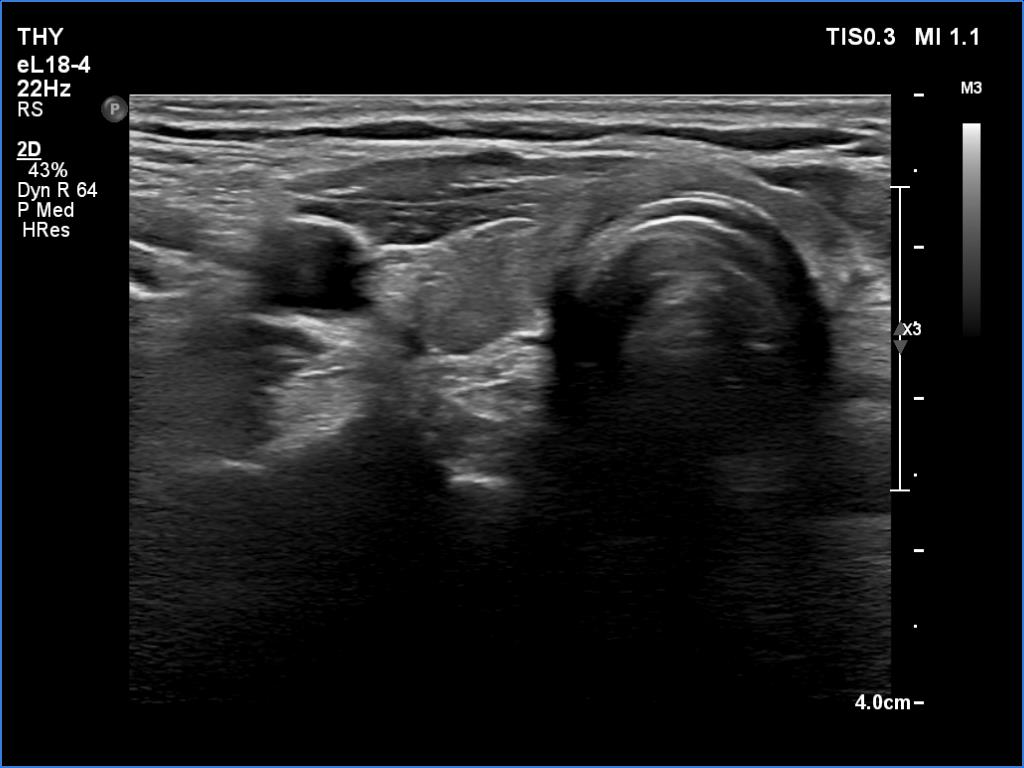

First examination (first row of images):

Clinical presentation: A 38-yr-old woman requested evaluation. She was treated for subacute de Quervain's thyroiditis with methylprednisolone 17 years ago. Five years later, despite normal TSH level, thyroid replacement therapy was initiated on complaints suggesting hypothyroidism. In the last 3 weeks she occasionally felt pain in the left side of the neck. Her body temperature remained normal.

Palpation: The left lobe was hard and tender on palpation.

Laboratory tests: TSH 1.26 mIU/L on daily 75 microgram levothyroxine, CRP 1.5 mg/L (normal value < 5), aTPO 0.5 U/mL.

Ultrasonography. The thyroid was minimally hypoechoic. There was a small, discrete lesion in the upper pole of the right lobe. The left lobe had a larger and several tiny hypoechogenic lesions. The large lesion presented partly blurred, partly lobulated margins.

Cytology was performed from the large hypoechoic lesion in the left lobe and resulted in subacute, de Quervain's thyroiditis.

Suggestion: non-steroid anti-inflammatory drug, repeat examination in three months.